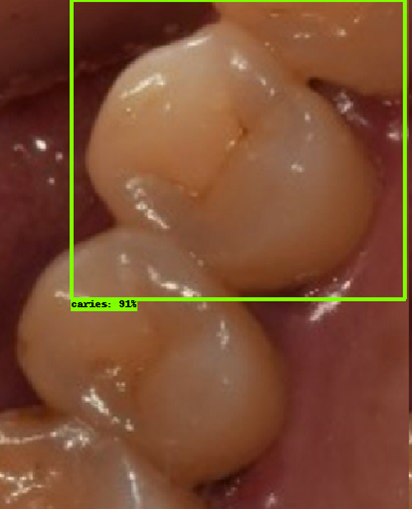

| 모델예측 | 정답 |

|---|---|

![]() |

- 인식이 잘 되지 않은 케이스들을 보면, 사람의 눈으로 뚜렷하게 충치로 판단되는 치아를 모델이 잡아내지 못하는 경우도 있었지만, 그보다는 사람의 눈으로도 충치로 분류하기 어려운 경우에 모델역시 잘 분류해내지 못하는 것을 볼 수 있었습니다. 예를 들어, 인식이 잘되지 않은 첫번째 케이스, 세번째 케이스를 보면 정답지에는 충치 치아로 분류되어 있지만, 사람이 한눈에 보기에도 충치라고 판단하기 어려운 사진들이었습니다. 이러한 경우에 모델은 잘 잡아내지 못하고 있습니다.